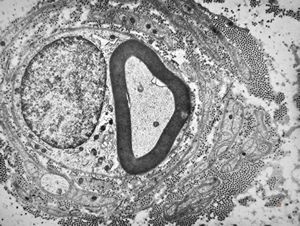

F,31y. | demyelinating hypertrophic neuropathy - n. suralis- bands of Büngner with collagen-filled pockets